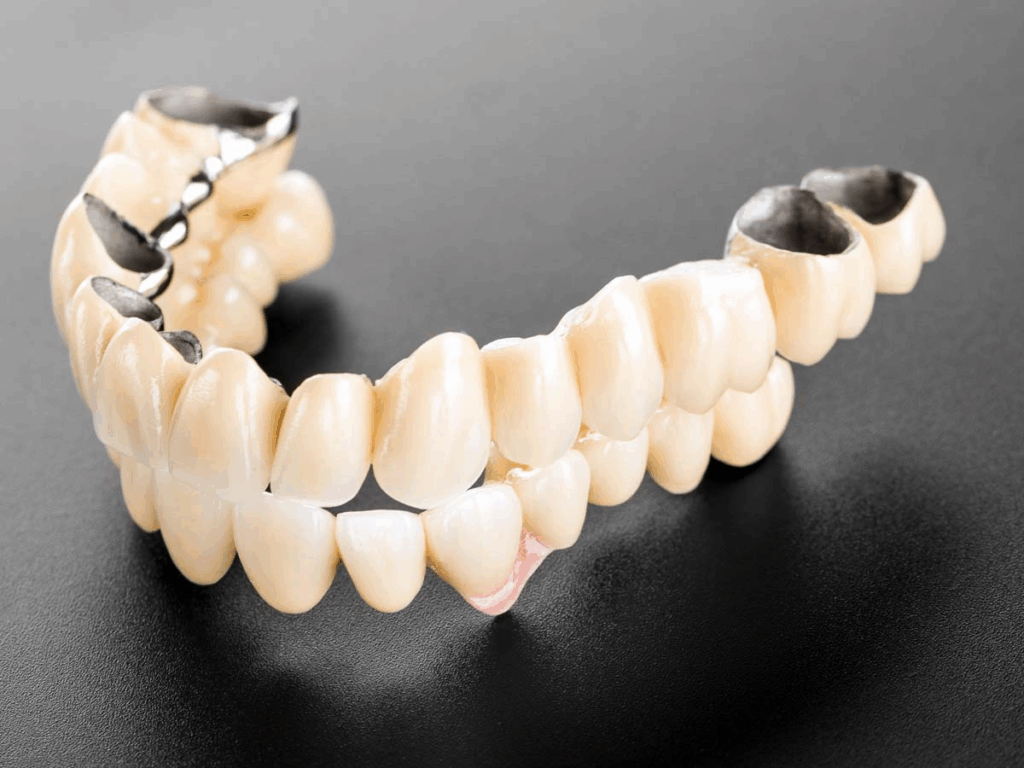

四、固定式傳統全口橋體(需磨牙)

技術原理

藉由磨剩餘牙齒做為橋樑支撐,連接假牙。

適合對象

- 有剩餘牙齒者

- 預算中等、不想植牙者

優點

- 視覺接近自然牙

- 穩定性高於活動假牙

缺點

- 需磨牙

- 齒槽骨仍會萎縮